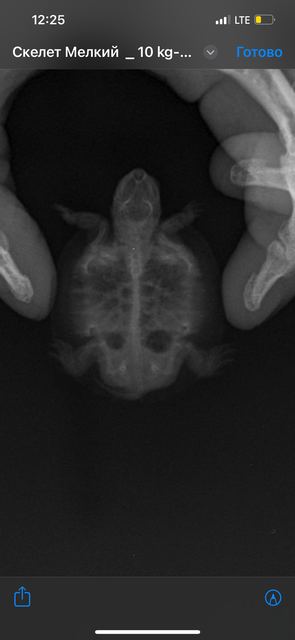

Если получится сделать рентген - желательно 3 проекции, или хотя бы две: под номерами 1 и 3. Чтобы можно было и лёгкие и жкт посмотреть. В проекции просто лёжа на животе лёгкие не видно. Везите либо в тканевом мешке с дырочками под одеждой, либо в переноске с грелкой, чтобы не замёрзла.

Здравствуйте. Ренген сделали.

IMG_7607.png

IMG_7606.png

IMG_7605.png

@lelka101 камней не видно, уже радует

@lelka101 врач посмотрела снимки и сказала, что есть помутнения в лёгких, нужен антибиотик. Закажите Марбобел 2%, воду для инъекций и 10 инсулиновых шприцев с шагом 0.01мл. Посмотрите, чтобы между числовыми делениями было 10 делений, а не 5. Черепашка маленькая - будет удобнее набирать, т.к. дозировка будет буквально капля.